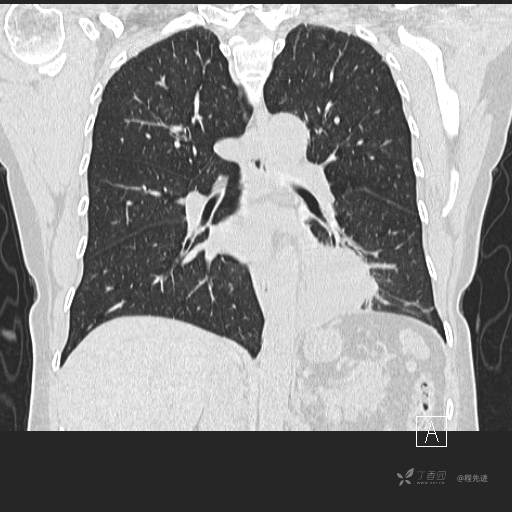

冠状位重建

CT值:平扫:31HU,动脉期:74HU,静脉期:84HU